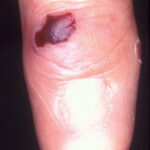

Tumors

SCC often arises in chronic cutaneous lesions in patients with epidermolysis bullosa. SCC often occurs at multiple primary sites, which is especially true for patients with recessively inherited epidermolysis bullosa.

In the non-epidermolysis bullosa population, cutaneous SCC arises most frequently in sun-exposed areas and primarily affects individuals with skin types I and II after the fourth decade of life.

In contrast, the distribution of cutaneous SCC in patients with recessively inherited epidermolysis bullosa is different. In recessively inherited epidermolysis bullosa, SCC affects all skin types, does not show a predilection for sun-exposed sites, and peak incidence begins to increase dramatically in the second and third decades of life. Recent studies on the pathogenesis of SCC in recessively inherited epidermolysis bullosa patients suggest that it arises from retained expression of the type VII collagen NC1 domain.12 Type VII collagen is required for Ras-driven human epidermal tumorigenesis.

- SCC: Arising in chronic wounds or scars of recessively inherited epidermolysis bullosa, this form of SCC is invasive and has high metastatic potential. Other epidermolysis bullosa subtypes do not show a tendency to develop SCC.